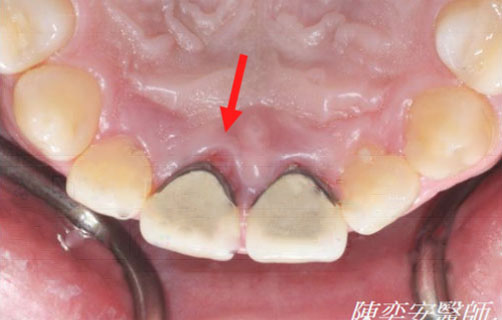

牙周再生手術 — 填補骨粉&再生膜

治療前

門牙顎側牙肉反覆腫脹

牙齦紅腫,骨缺損近2/3